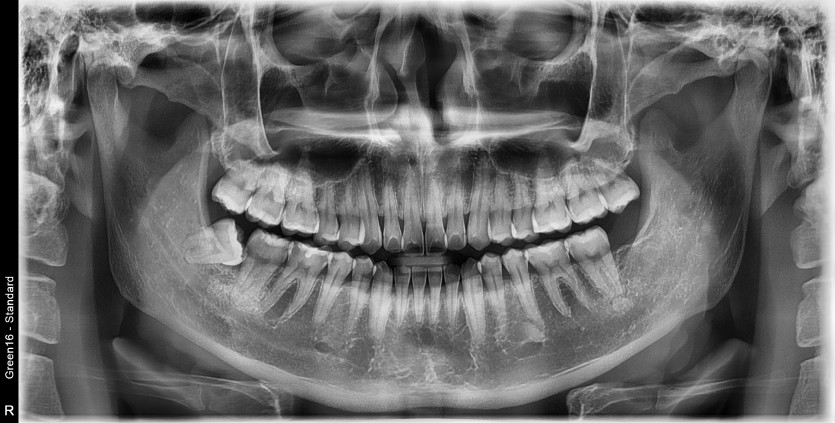

#18,48 사랑니 발치

구강 외과 전문의가 당일 발치했습니다.